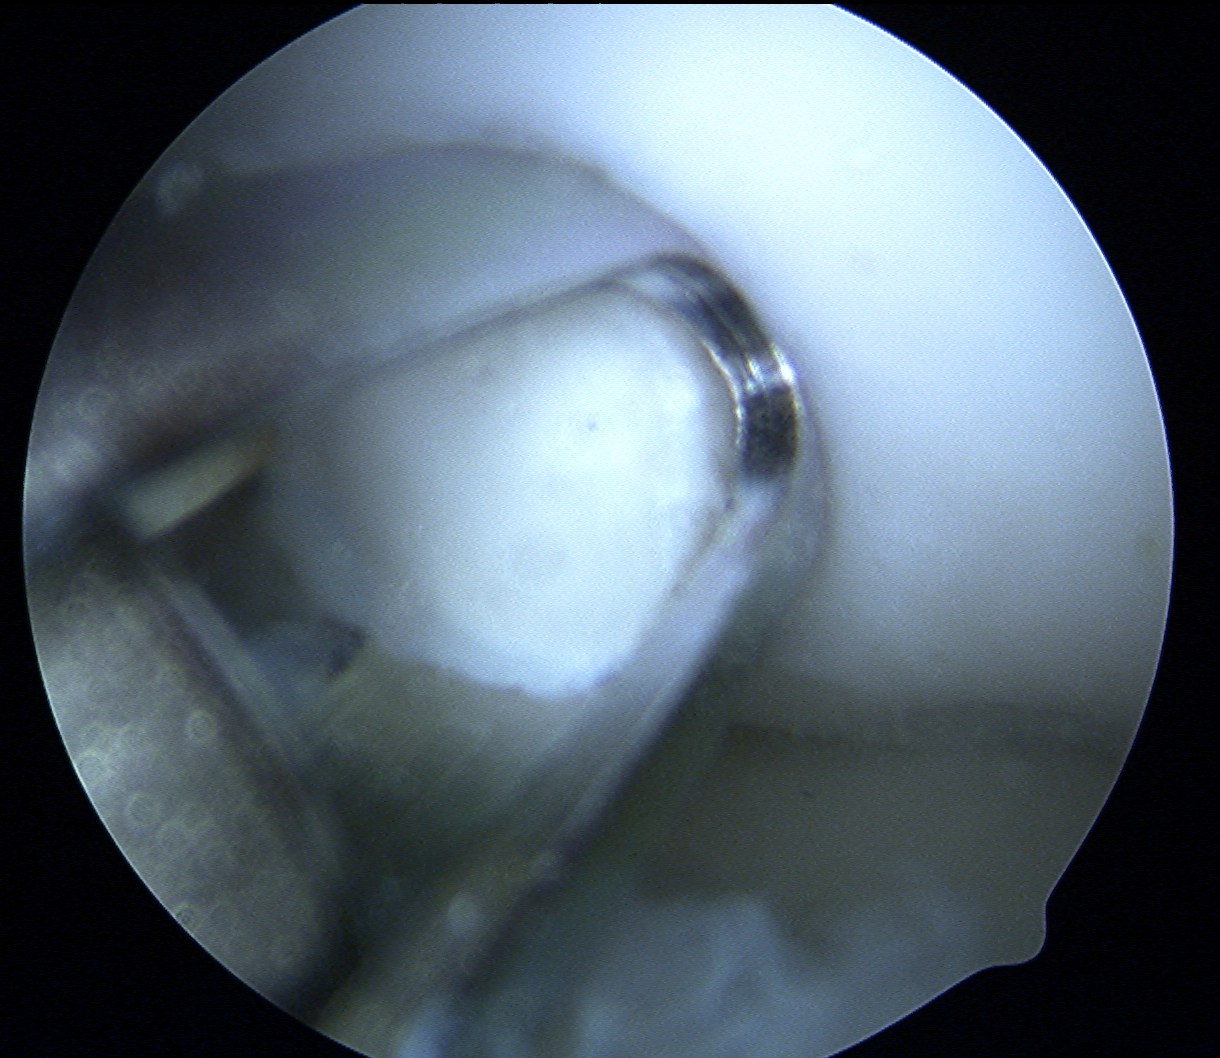

Repeat

Post op

Often most stable in extension

- splint in extension 2 weeks

- gentle increased ROM in brace over next 4 weeks

- strict NWB 6/52

Allow weight bearing at 6/52

- no sports for 6/12

- MRI cartilage sequences at 3 and 6 months to assess cartilage healing